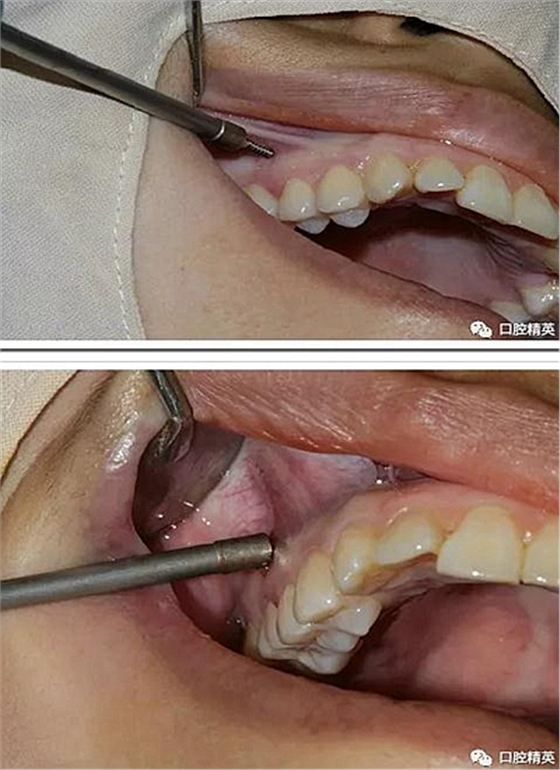

再次,植入微型種植體,在附著牙齦處不需要粘骨膜翻瓣,在牙槽黏膜處則需要切開黏膜以避免植入時(shí)軟組織被卷入,植入部位通常在膜齦結(jié)合部位或偏根方2~3mm,植入角度與骨面垂直并傾斜15~20度,即向根尖方向植入,術(shù)后拍根尖片以確認(rèn)與牙根的關(guān)系。術(shù)后口服抗生素預(yù)防感染并進(jìn)行口腔衛(wèi)生宣教。

2、助攻型種植釘,上頜與頜骨成30-40°角,下頜與頜骨成10-20°角(目的:1、降低損傷牙根及牙周膜的機(jī)率;2、使種植釘盡量植入骨皮質(zhì)內(nèi),降低松動機(jī)率);自攻型種植釘與頜骨垂直;個(gè)人習(xí)慣:自攻型種植釘上下頜均與頜骨成30-40°角。

3 、無論是助攻型還是自攻型種植釘,植入前分離粘骨膜步驟必不可少。軟組織的夾入是手術(shù)失敗的常見原因之一。